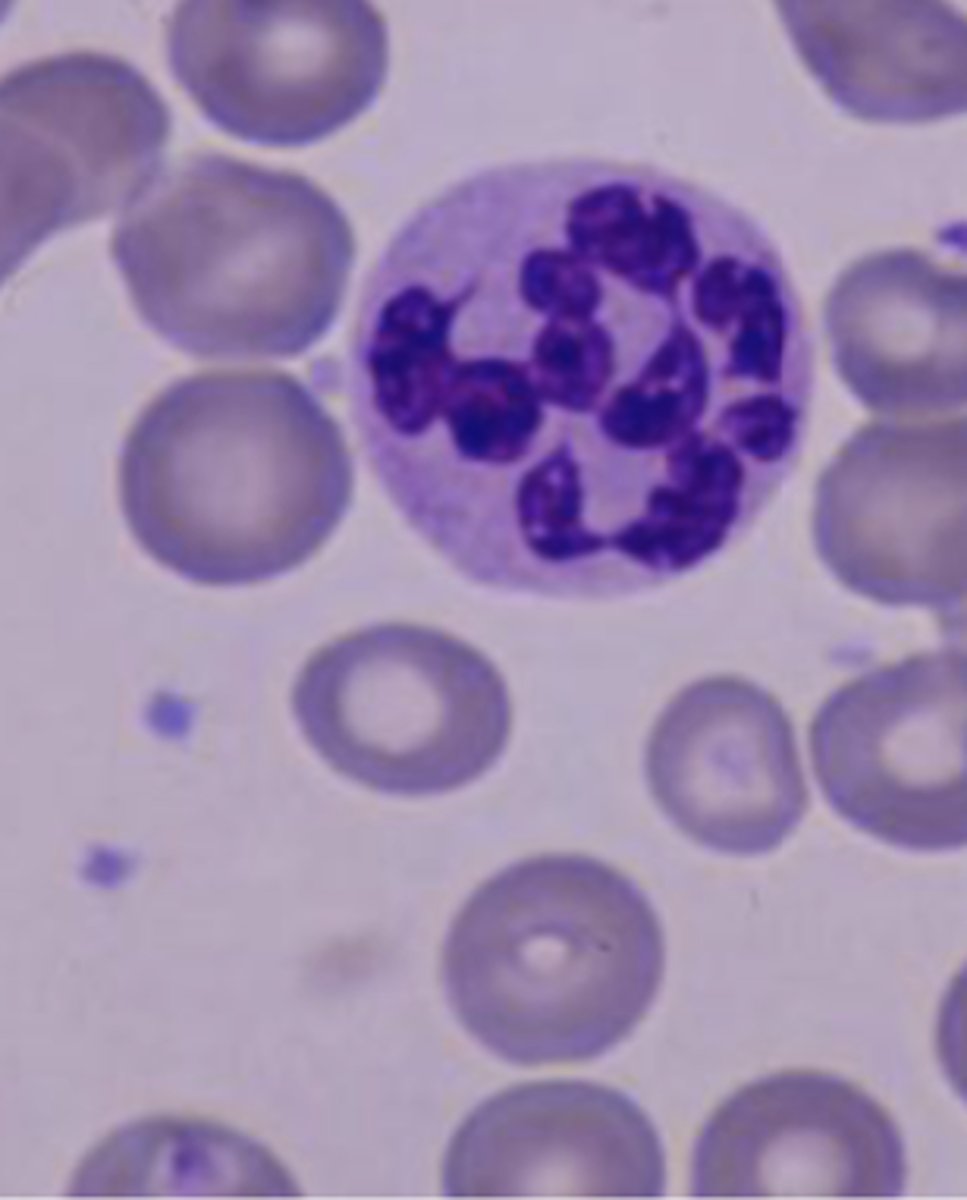

plasmodium

exotic hemoparasite

causes avian malaria

via mosquitoes